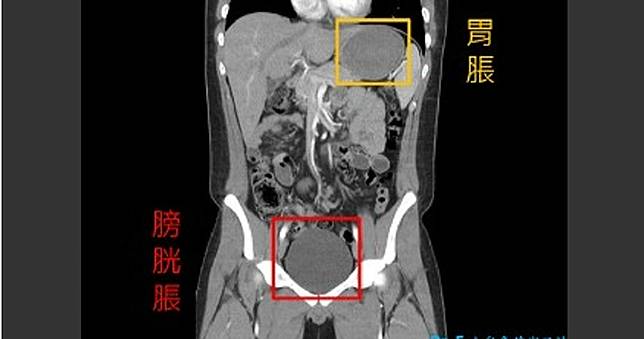

一名急診室主任在「Dr.E小兒急診室日誌」臉書粉專PO文,一名17歲高中生在挑戰完無敵麻辣麵後,腹部劇烈疼痛且無法順利排尿而送醫,「除上腹部疼痛外,他覺得膀胱很脹很痛,卻無法順利排尿,用力擠只能排出一點點尿液。」醫生檢查後判斷是因辛辣食物造成胃酸分泌過多,且胃部被極度撐大才造成疼痛,經注射胃部制酸劑,加上藥物和灌腸,疼痛才逐漸緩解。